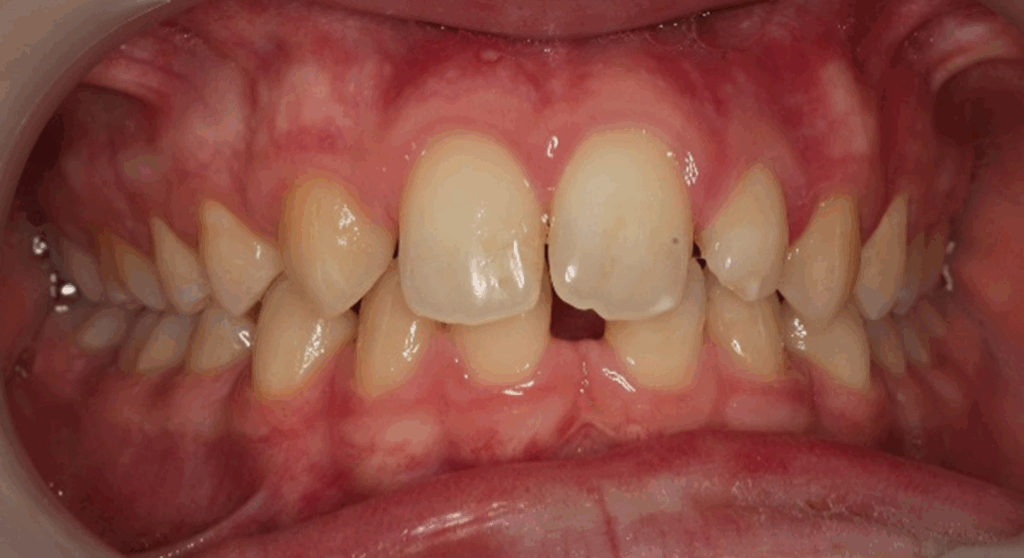

Age: 12 years

Main complaint: Aesthetic concerns and functional difficulties

Skeletal Class II due to mandibular retrognathia, proclination of maxillary incisors, narrow arch creating a V-shaped arch, agenesis of 12, 31, 41, hyperdivergent facial pattern, moderate deep bite (2 mm), increased overjet (9 mm), asymmetric canine and molar Class II due to mandibular deviation to the left, maxillary midline deviation related to agenesis of 12, distal rotation of 35 and 45, and pronounced lower curve of Spee.

Labial incompetence, mouth breathing, tongue dysfunction